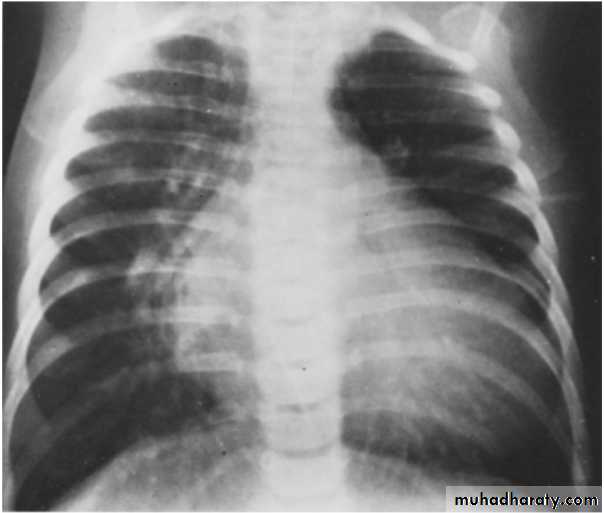

VENTRICULAR SEPTAL DEFECT (cont.)

• X-ray findings• small VSD normal

• large VSD cardiomegaly, dilated pulmonary vessels (plethoric lung)

1. LV and RV enlargement with Left ventricular type

2. Pulmonary vasculature is increased.

3. Prominent PA segment

4. Normal or smaller aorta